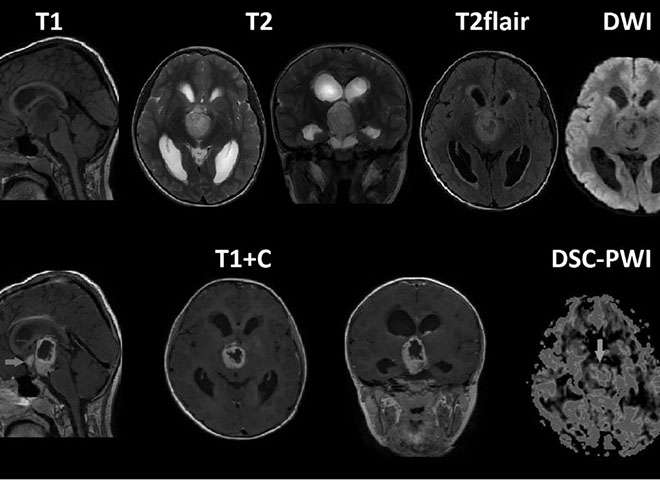

Т1 т2 flair

Т1 т2 flair 116 фотографий